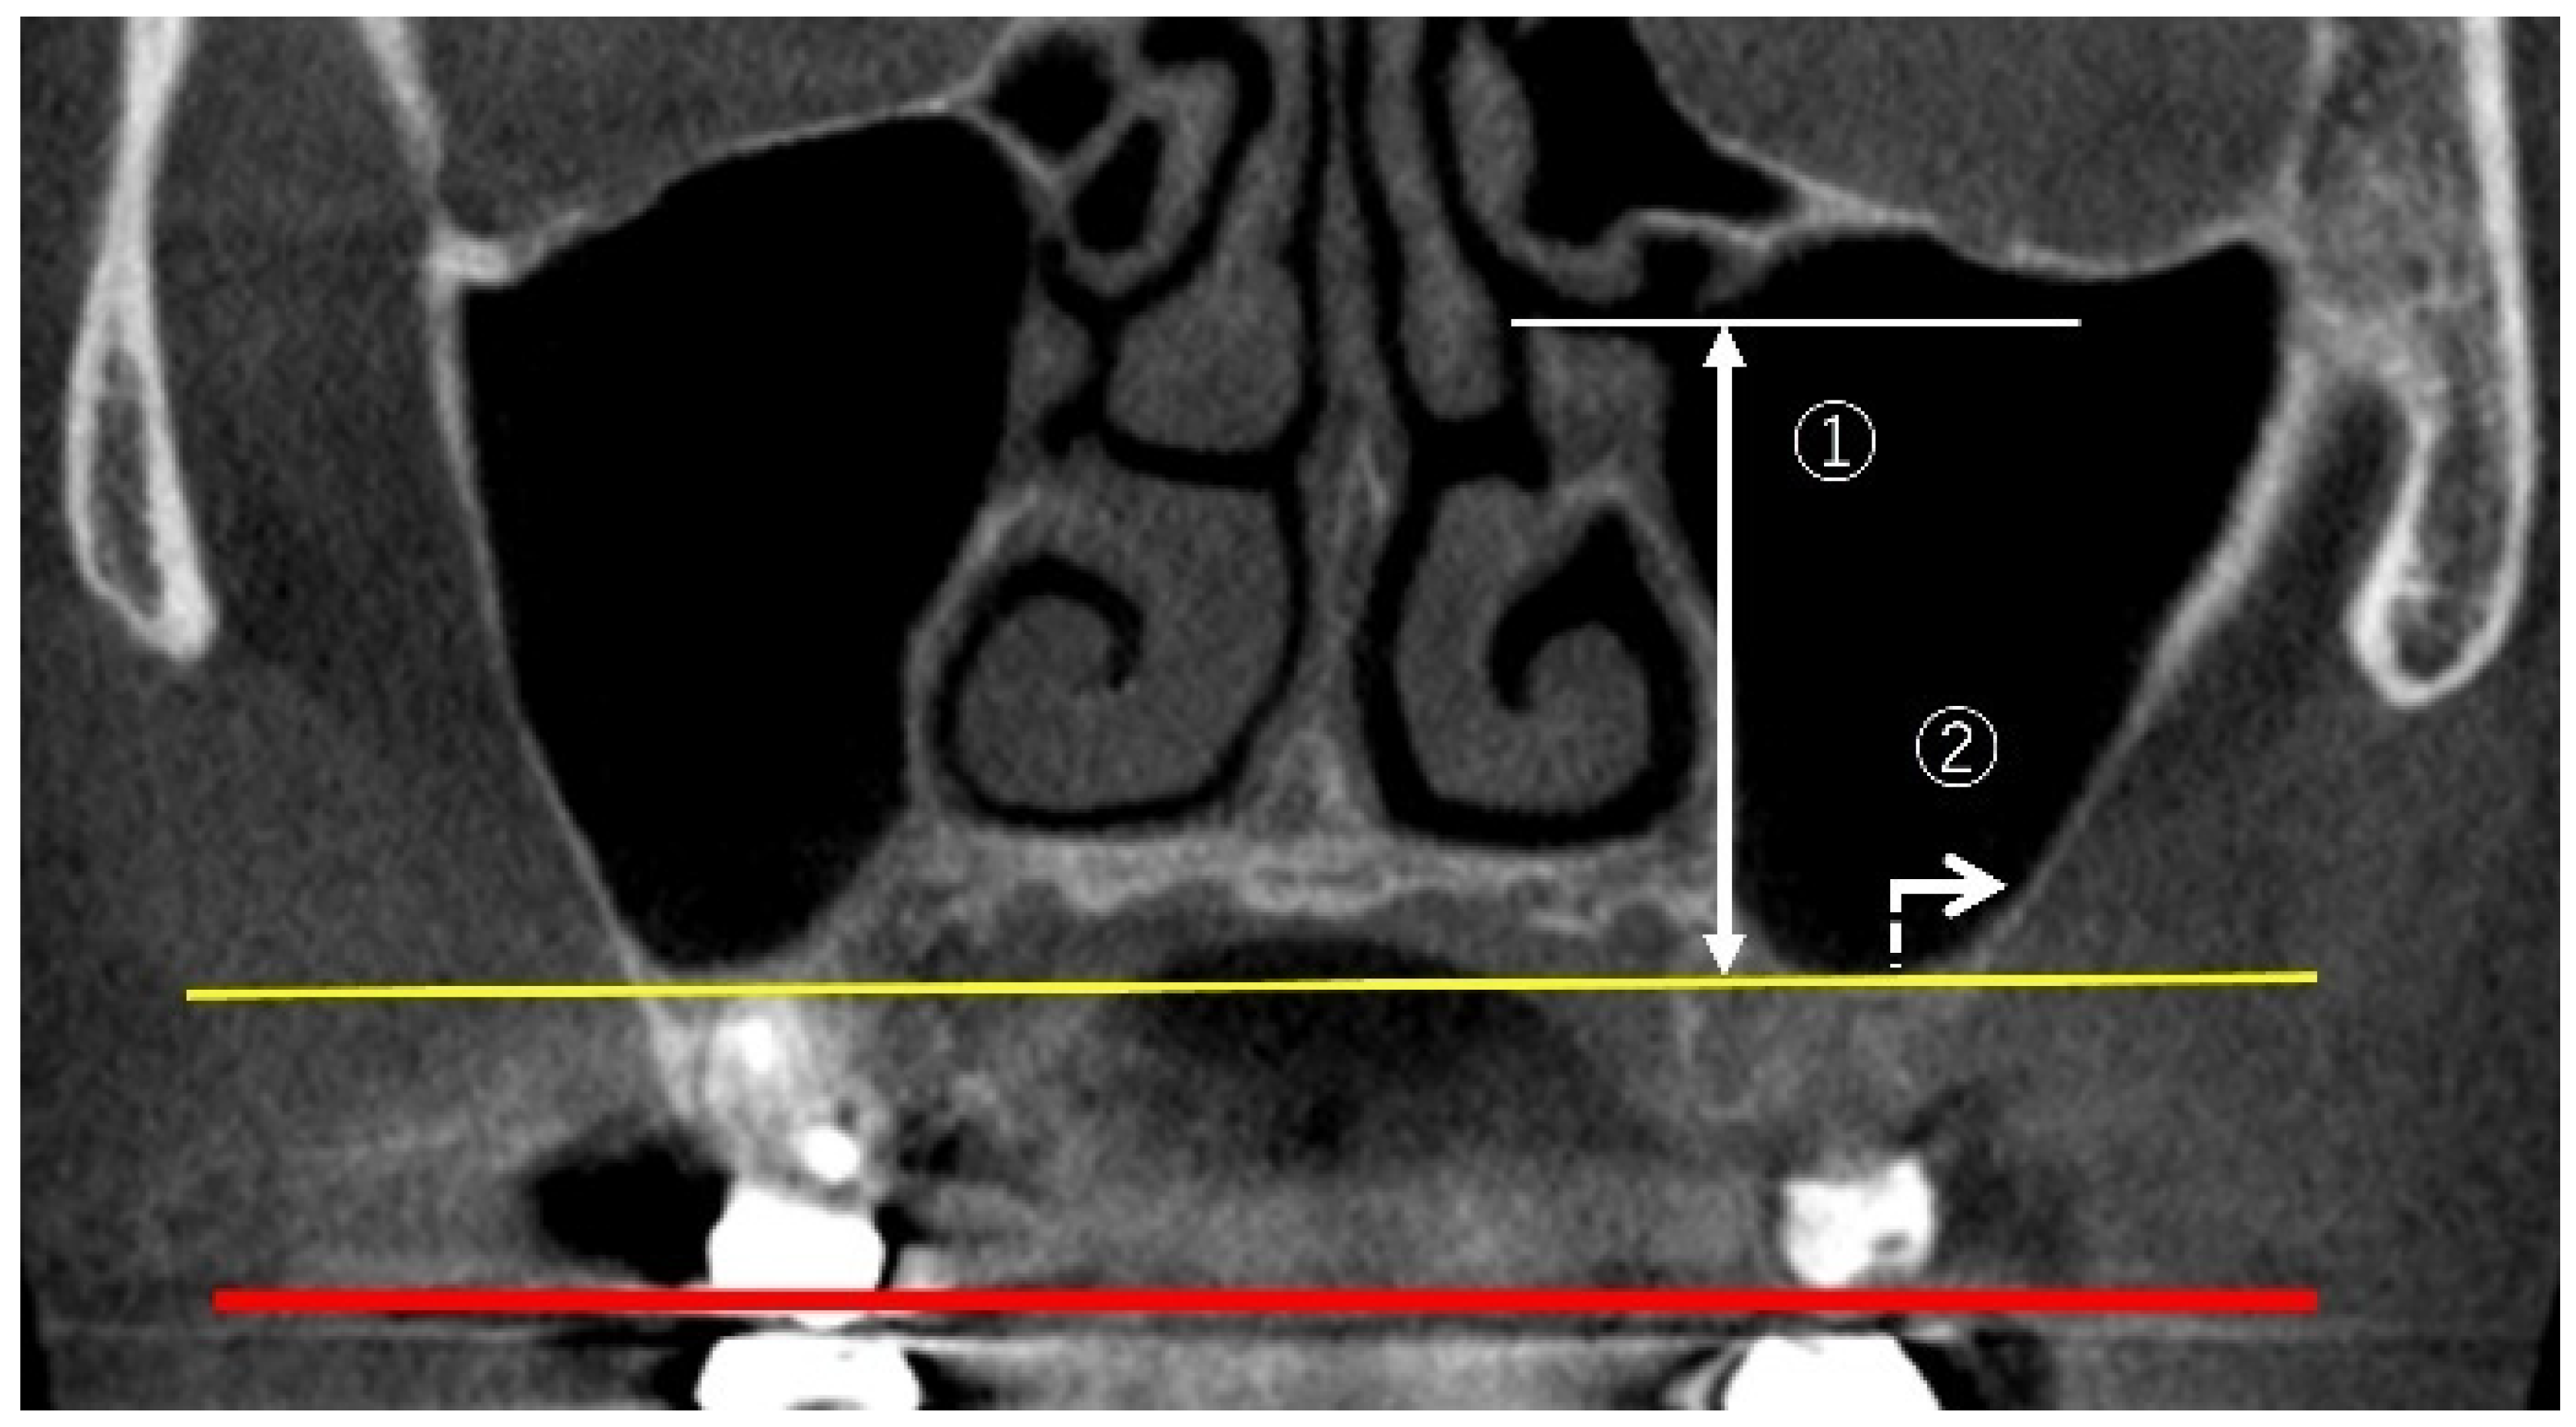

2.2. Measurement Method Using CBCT Images

2.3. Measurement Items

2.3.1. Linear Measurements of Maxillary Sinus Height

2.3.2. Measurement of PNR Angle and Maxillary Sinus Angle (MSA)

2.3.3. Measurement of Sinus Membrane Thickness (SMT)

2.3.4. Linear Measurements of Maxillary Sinus Length